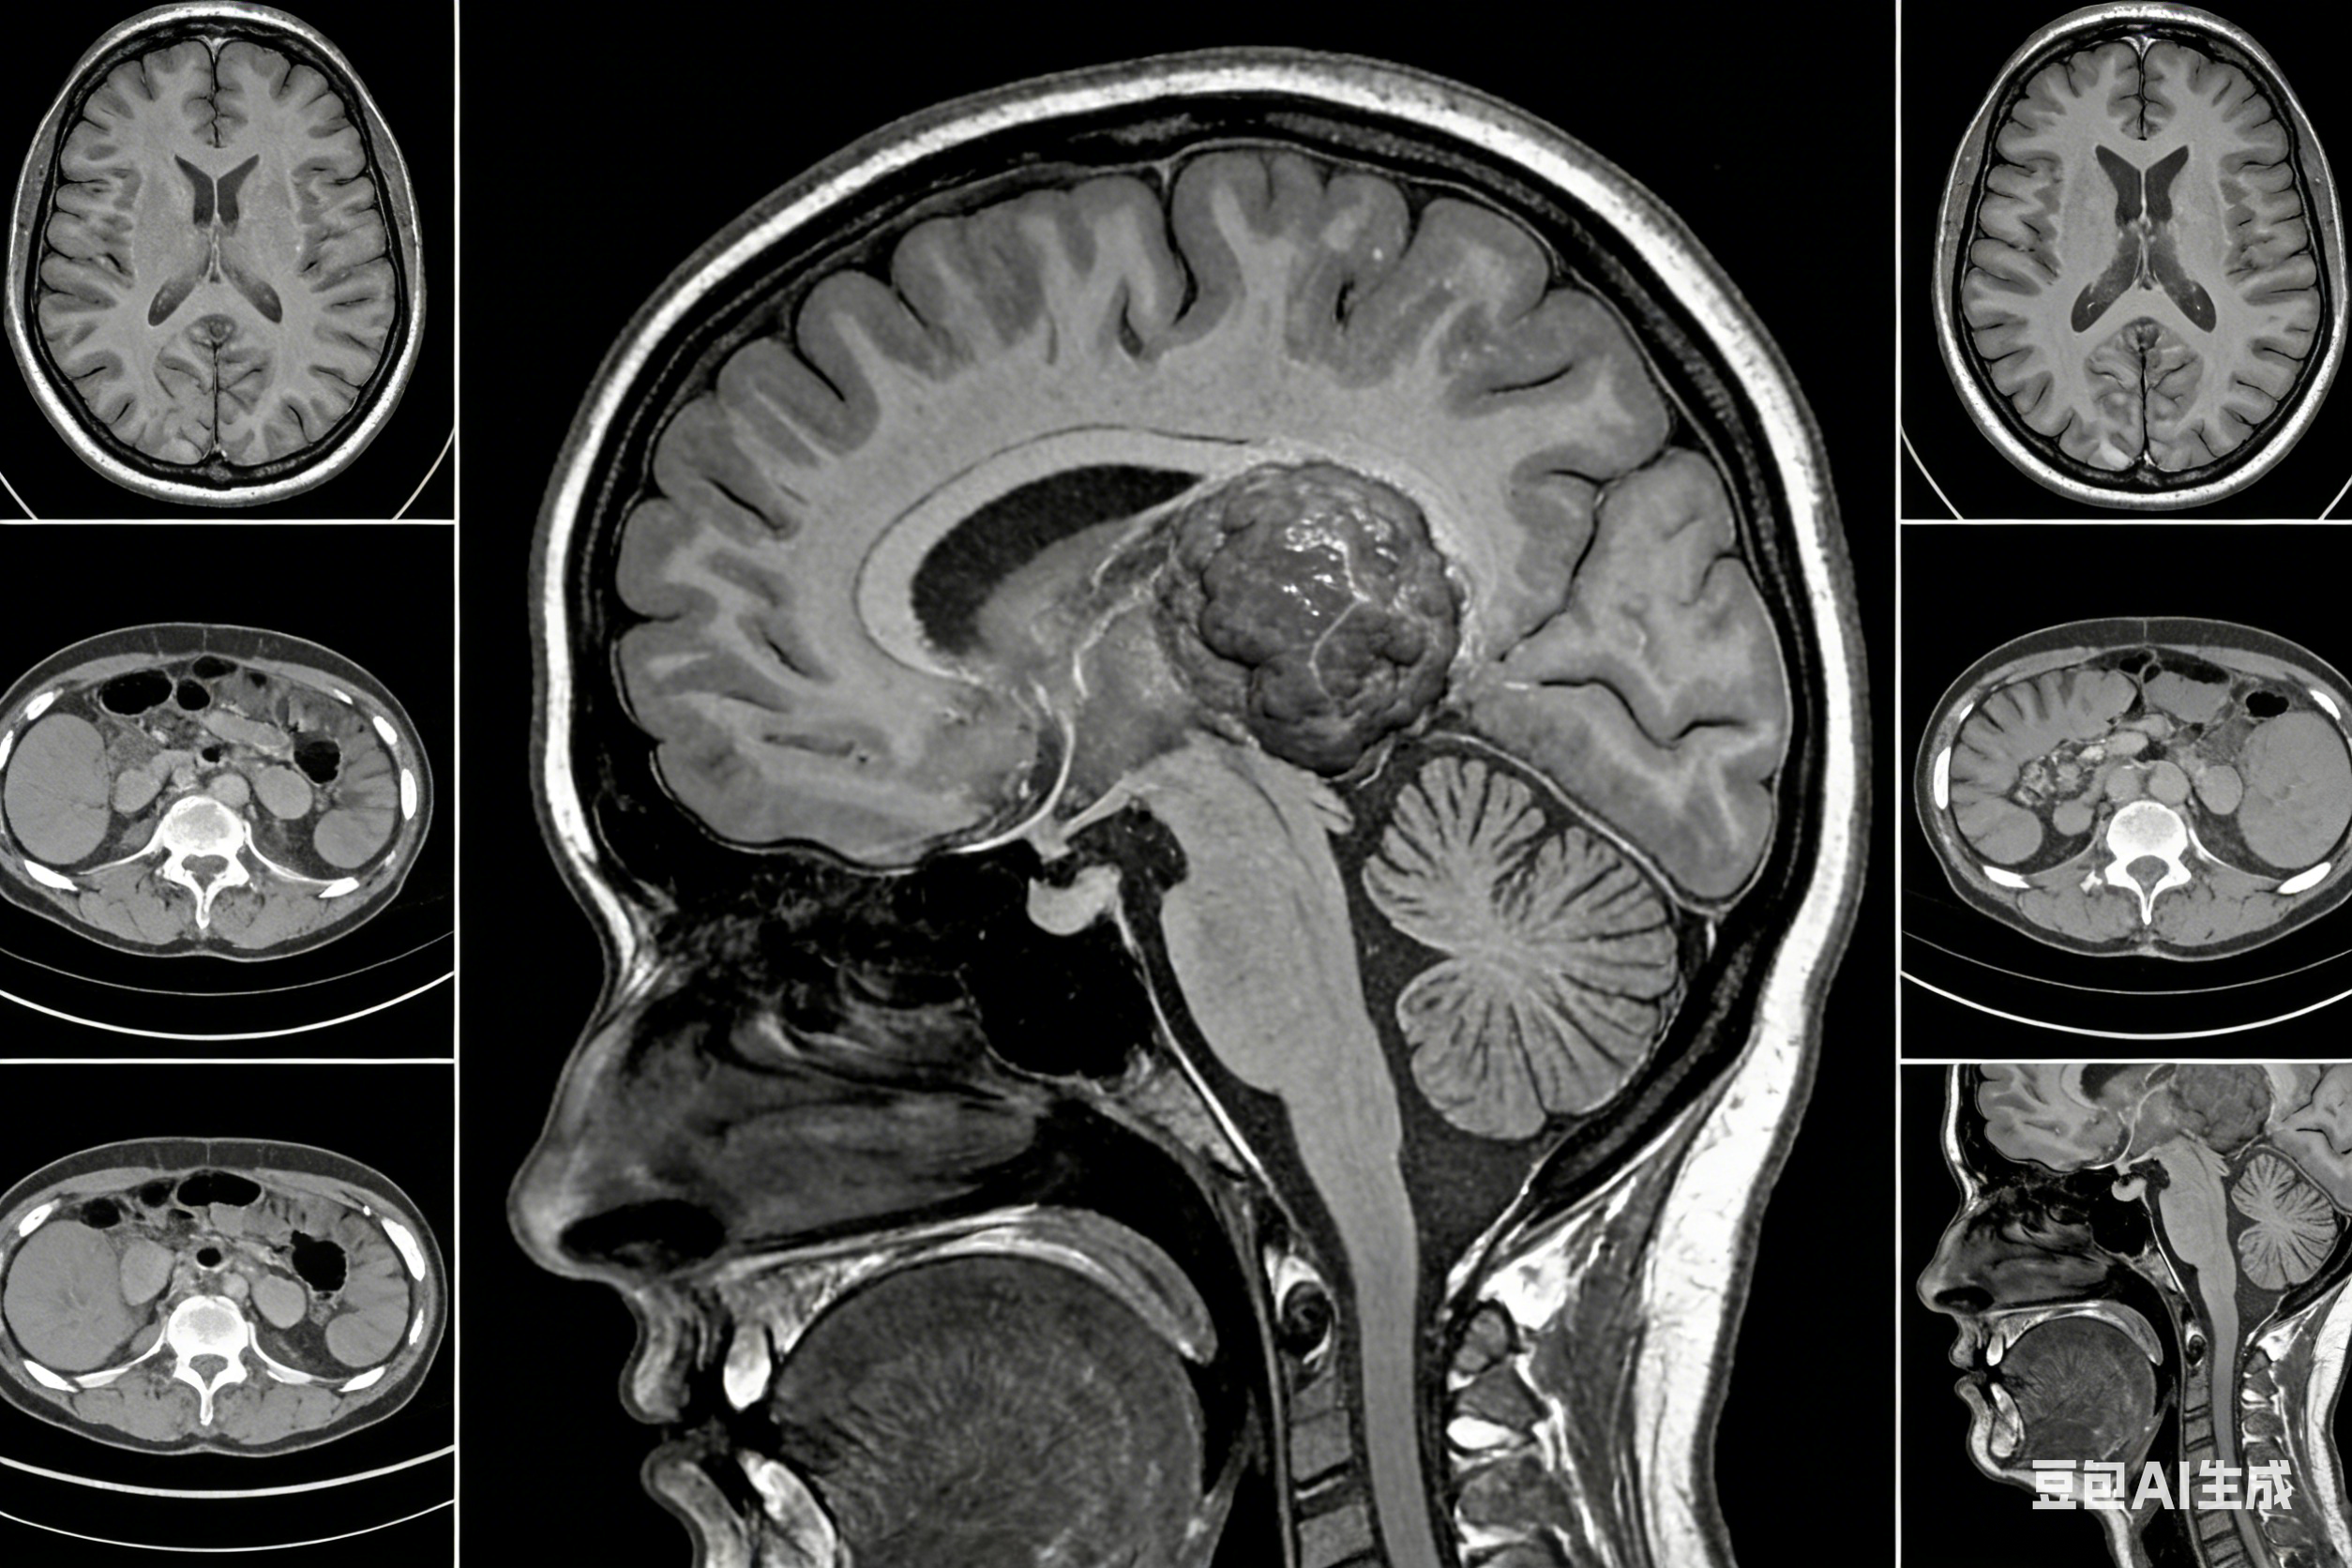

天津市环湖医院头颈神经肿瘤中心成立于2022年7月1日。以神经系统良、恶性肿瘤、头颈肿瘤及相关体部肿瘤的多学科综合治疗为特色。中心整合全院神经外科、眼耳鼻咽喉头颈外科、肿瘤化疗、放疗、介入微创、病理、影像、康复等多学科团队优势,协调联动,建立环湖医院特色的头颈神经肿瘤综合诊疗体系,为肿瘤患者提供高水平、同质化的医疗服务,最终实现让肿瘤患者“保功能、提高生活质量、延长生存期”,打造国内领先、国际水平的头颈神经肿瘤高水平学科群。天津市环湖医院脑胶质瘤病房作为治疗神经肿瘤专业的特色专业组,主要从事颅内肿瘤的显微外科及神经内镜手术治疗,包括胶质瘤、脑膜瘤、垂体瘤、脑转移瘤、神经鞘瘤等。持续加强专科建设,保持优势学科,扩大病源,提高手术质量,降低并发症发生率,将神经肿瘤专业“做大,做强,做精”。